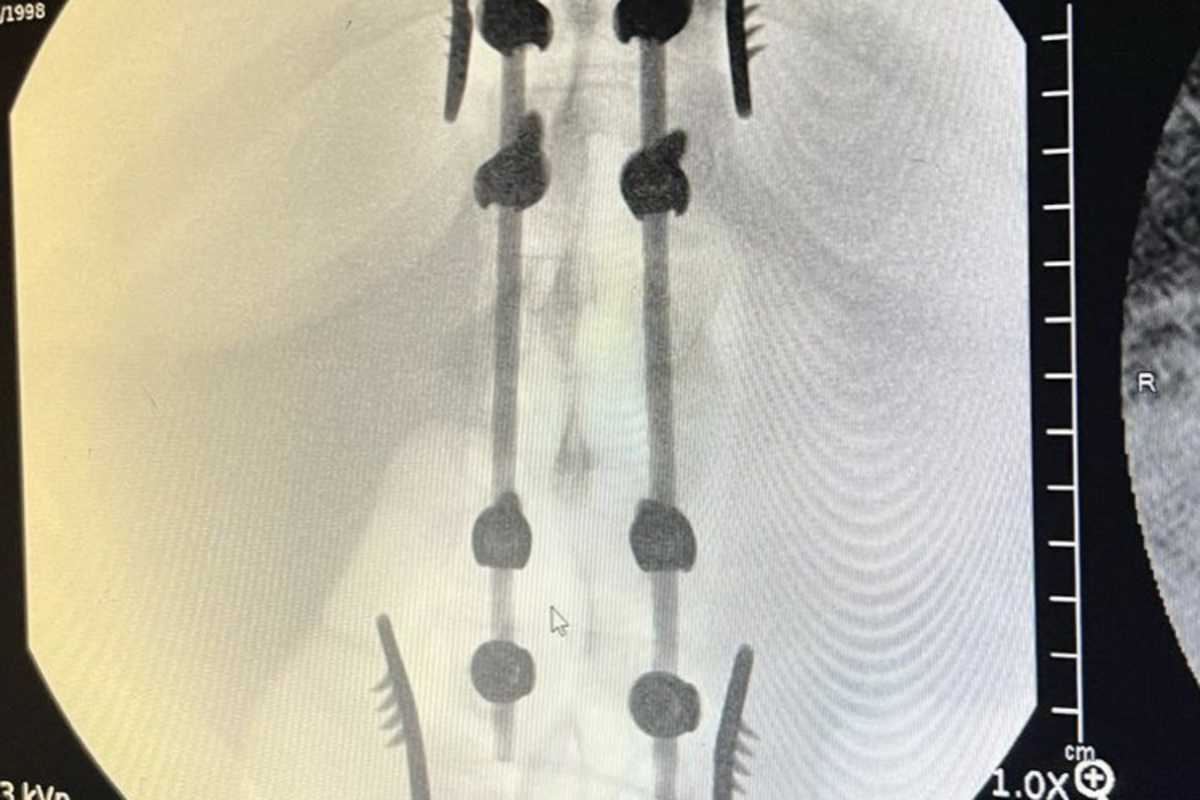

"Es geschah in einer Rhythmussektion von 3 Dreifachsprüngen", erklärte Hartranft. "Ich bin am zweiten Sprung mit dem Kopf voran eingeschlagen." Er zog sich mehrere Wirbelbrüche zu: Die Lendenwirbel L1 und L2 sind gebrochen. Die Querfortsätze der Lendenwirbel L3 und L4 sowie die Dornfortsätze der Lendenwirbel L1, L2 und L3 sind gebrochen. Das linke Hüftgelenk ist ausgekugelt. Außerdem sind mehrere Rippen und das rechte Schulterblatt gebrochen. Zudem hat er einen Hämatothorax erlitten.

Hartranft wurde am Donnerstag operiert, um die Wirbelsäulenverletzungen zu stabilisieren. Sein Zustand ist stabil und hat Gefühl in den Beinen.